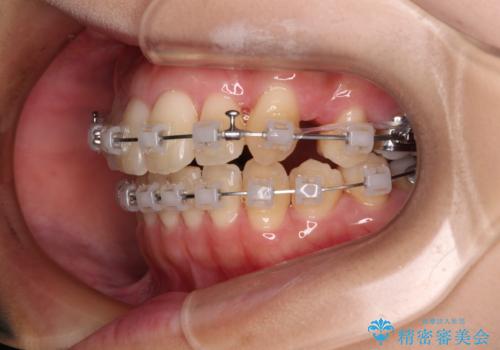

八重歯を改善 ワイヤー装置での抜歯矯正

- クリアブラケット

下顎歯列の叢生は軽度であることと、口元の突出感が全くなかったことから、八重歯解消のために上顎左右第一小臼歯を抜歯し、ワイヤー装置にて矯正治療を行うこととしました。

八重歯をスムーズに解消するために、補助装置を用いることで速やかに歯列を整えることができました。